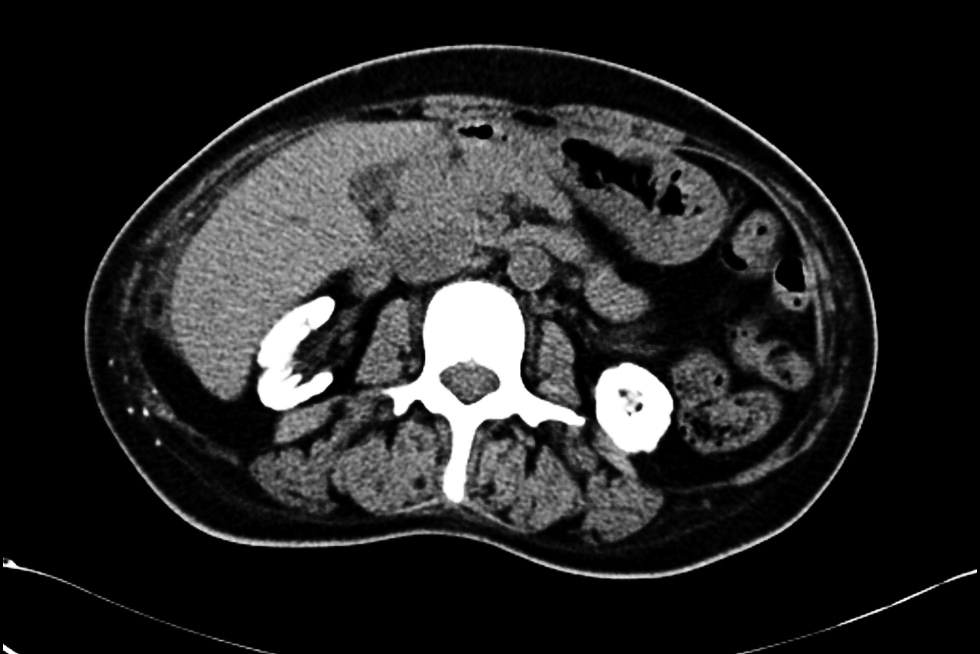

• 图3 患者双肾萎缩钙化及全身广泛骨质密度增高(腹部CT平扫)